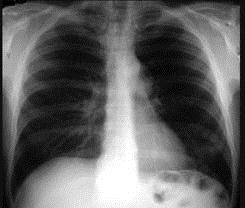

问题 47岁,男,腹泻、体重下降,伴有重症肌无力,请结合胸片和CT选择最可能的诊断 ( )

选项 A、纵隔血肿 B、错构瘤 C、胸腺瘤 D、淋巴瘤 E、胸腺增生

答案 C